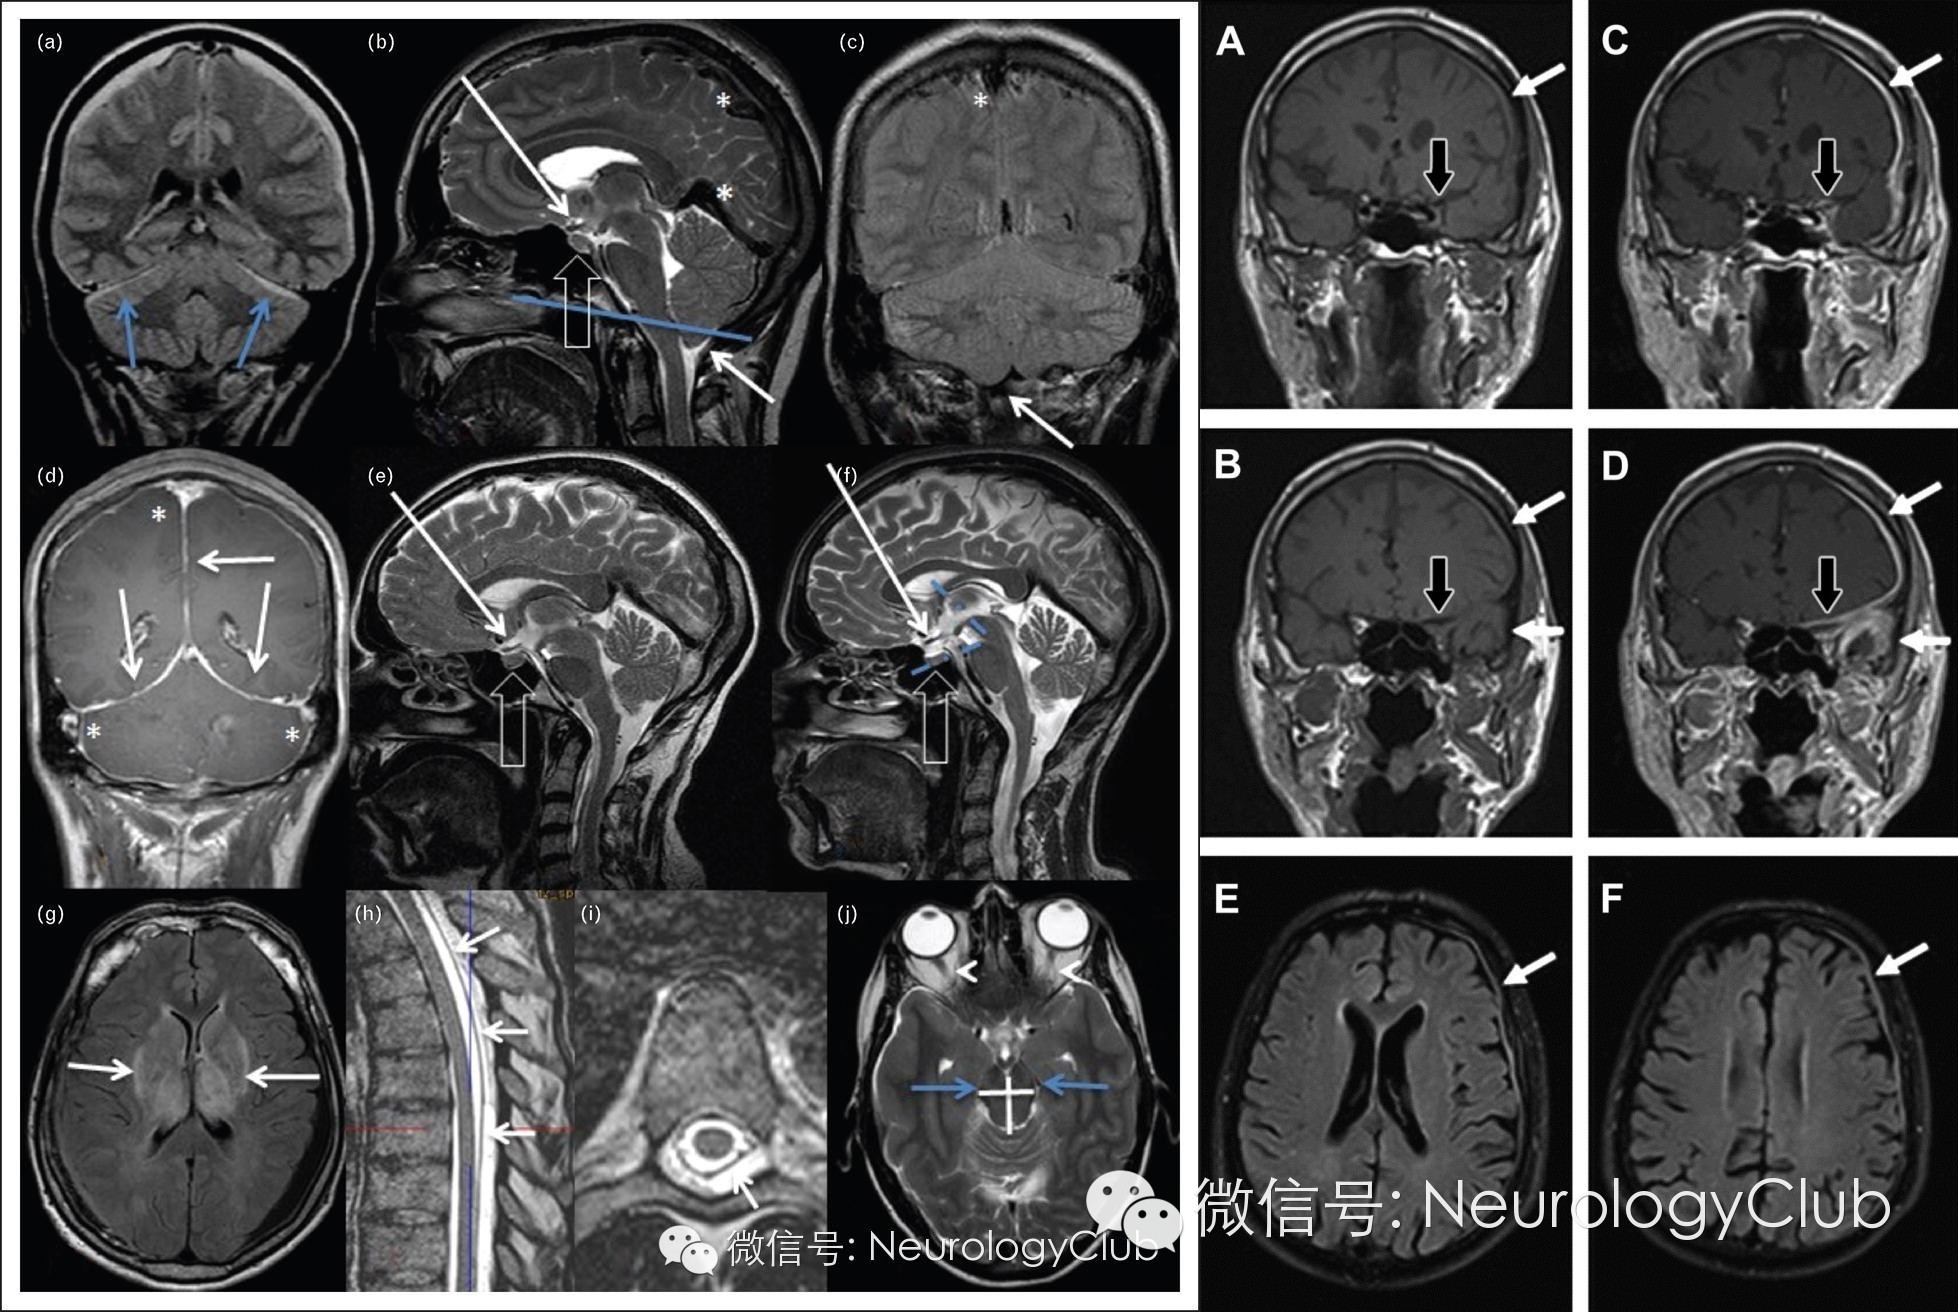

自发性低颅压综合征与肥厚性硬脑膜炎临床及影像学比较

自发性低颅压综合征(Spontaneous Intracranial Hypotension Syndrome)是一组以体位性头痛和脑脊液压力降低为特征的临床综合征。肥厚性硬脑膜炎(Hypertrophic Cranial Pachymeningitis)则是以颅内硬脑膜弥漫性肥厚和纤维化为特征的炎性反应性疾病。两者均以头痛为主要临床表现,且在影像学上均可表现为硬脑膜弥漫性增厚并异常强化,是硬脑膜病变的两种常见原因,临床鉴别时易产生混淆。

(左图a-j:自发性低颅压综合征;右图A-F:肥厚性硬脑膜炎